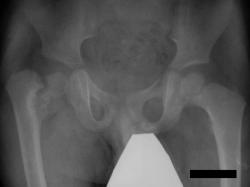

Нет, травмы в данном случае не было. Имеет место дистрофическая coxa vara, вероятнее всего, врождённаяю. Эпифизеолиз головки, который мы видим на снимке, как мы считаем, наступил вследствие нарушений биомеханики в суставе - ШДУ практически 90 градусов. Добавлю, что факт травмы родители категорически отрицают. Ребёнок постепенно начал хромать, хромата усиливалась на протяжении 6 месяцев.